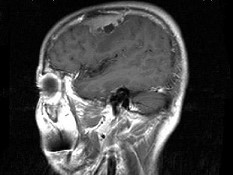

男,48岁,发作性口角抽搐半月,根据所提供图像,最可能的诊断是()

男,48岁,发作性口角抽搐半月,根据所提供图像,最可能的诊断是()

[单选题]男,48岁,发作性口角抽搐半月,根据所提供图像,最可能的诊断是()A . 右额叶胶质瘤B . 右额叶非典型脑膜瘤C . 右额叶骨瘤D . 右额叶炎性肉芽肿E . 右额叶转移瘤

- 查看答案